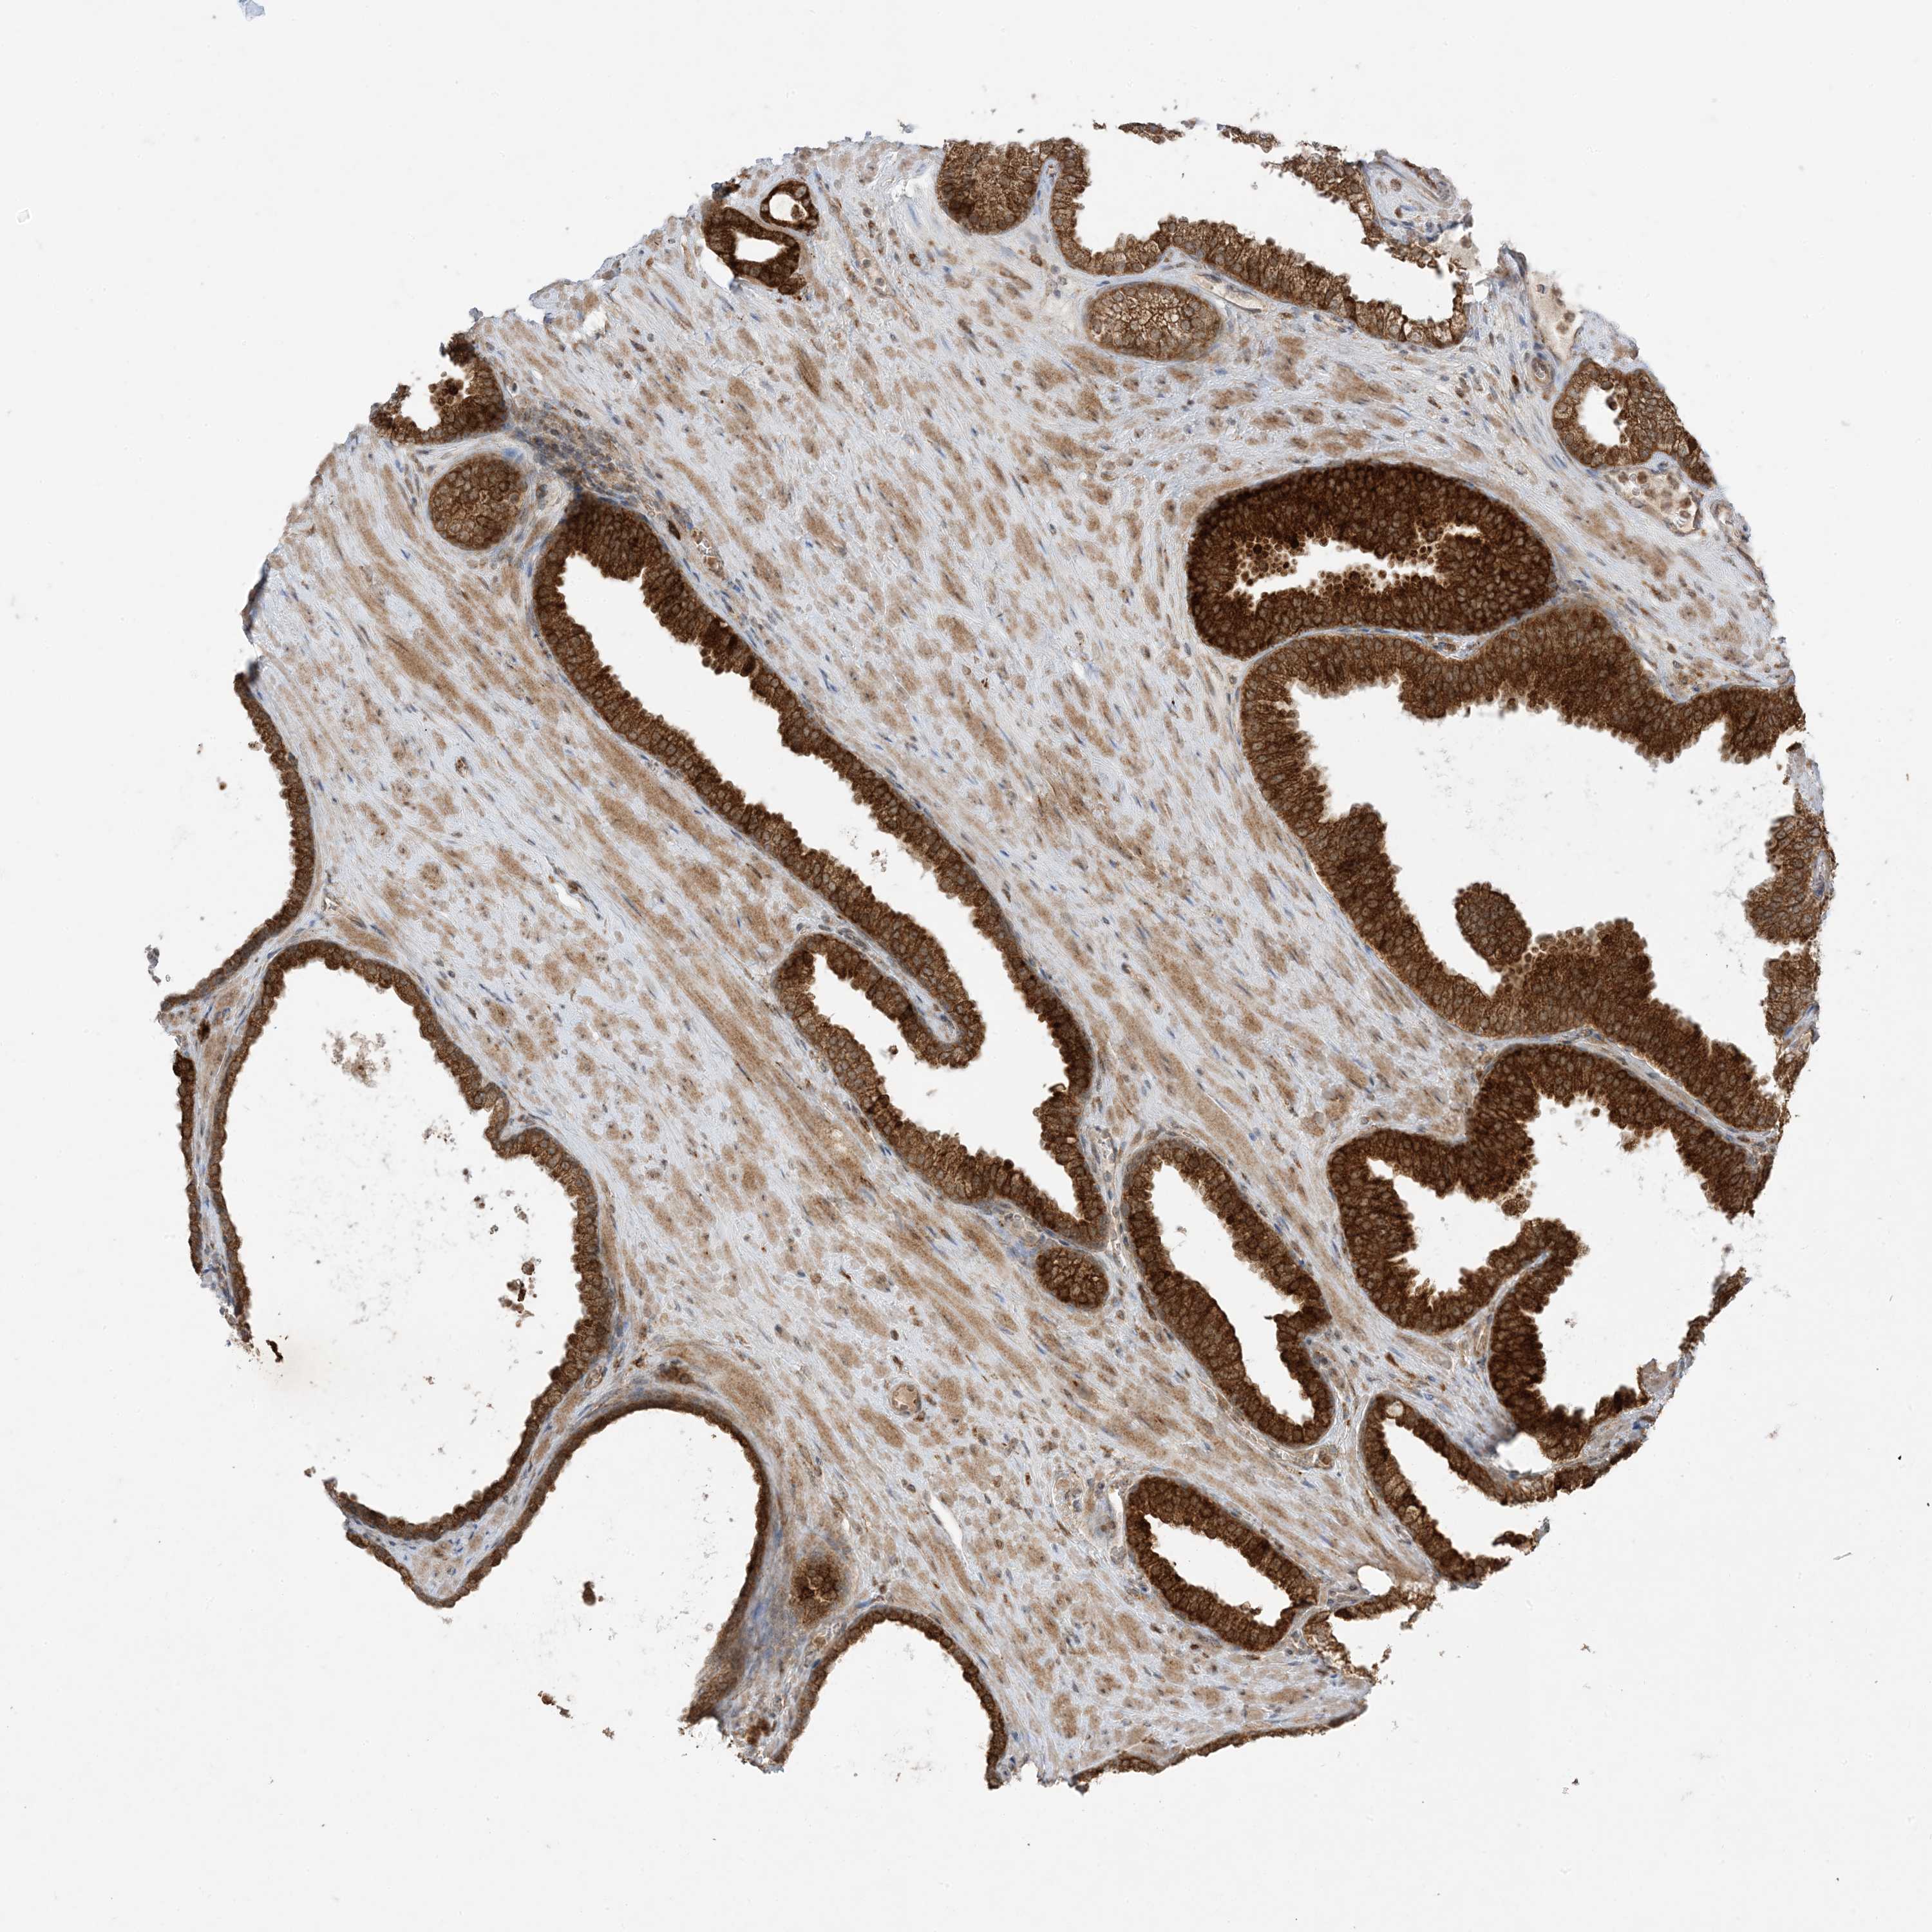

PROSTATE CANCER - Protein expressioni

A mouse-over function shows sample information and annotation data. Click on an image to view it in a full screen mode. Samples can be filtered based on level of antibody staining by selecting one or several of the following categories: high, medium, low and not detected. The assay and annotation is described here.

Note that samples used for immunohistochemistry by the Human Protein Atlas do not correspond to samples in the TCGA dataset.

Antibody stainingi

Antibody staining in the annotated cell types in the current human tissue is reported as not detected, low, medium, or high, based on conventional immunohistochemistry profiling in selected tissues. This score is based on the combination of the staining intensity and fraction of stained cells.

Each image is clickable and will lead to virtual microscopy that enables deeper exploration of all samples and also displays staining intensity scores, fraction scores and subcellular localization as well as patient and tissue information for each sample.

Antibody HPA001536

Antibody CAB035996

Staining

High

Medium

Low

Not detected

Intensity

Strong

Moderate

Weak

Negative

Quantity

>75%

75%-25%

<25%

None

Location

Nuclear

Cytoplasmic/membranous

Cytoplasmic/membranous,nuclear

Adenocarcinoma, Medium grade

Adenocarcinoma, High grade

Adenocarcinoma, Low grade